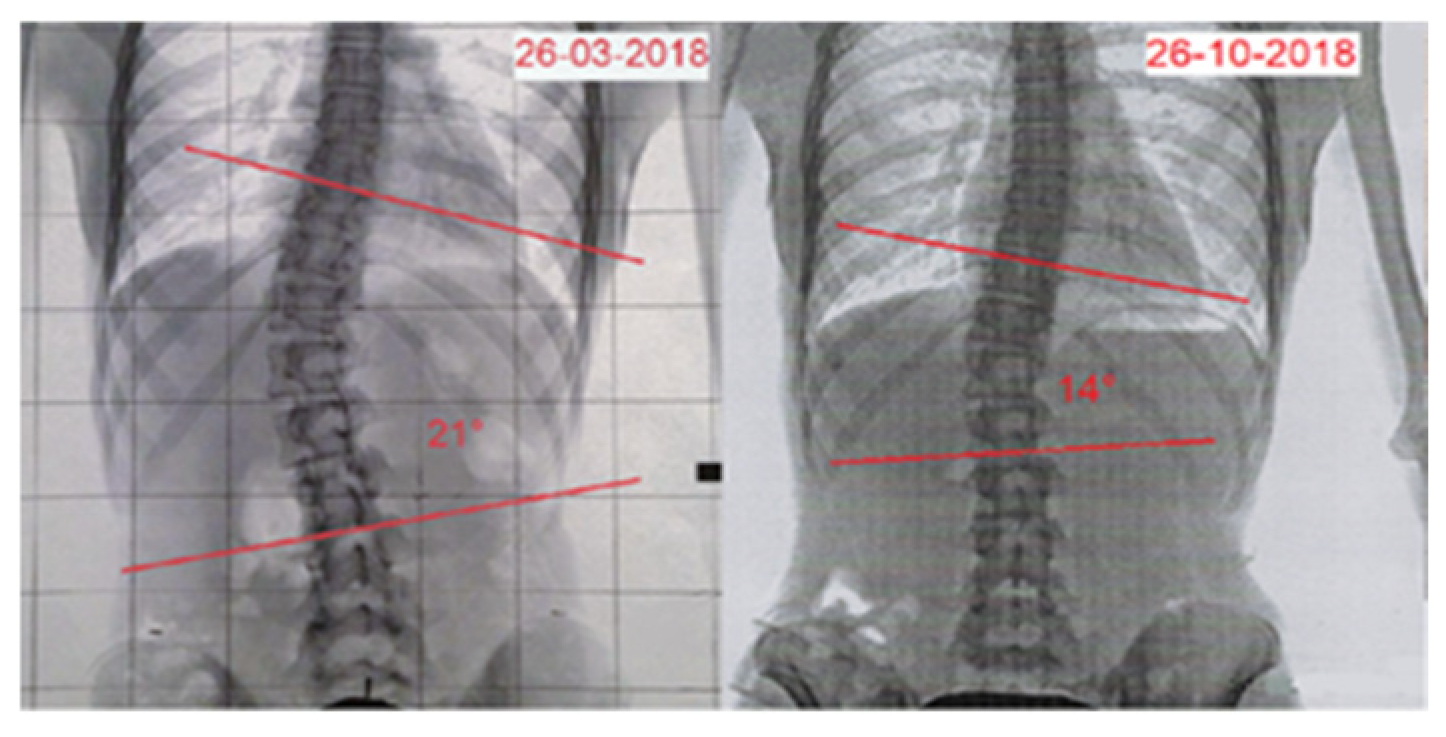

| Time | Age | Standing Height | Sitting Height | Weight | Cobb Angle | Risser | ATR | SRS-22 | TRACE |

|---|---|---|---|---|---|---|---|---|---|

| Pre | 13.4 | 156 cm | 81 cm | 42 kg | 21° | 2/3+ | 10° | 2.27 | 8 |

| Post | 13.11 | 157 cm | 82 cm | 45 kg | 14° | 3/4+ | 8° | 3.05 | 4 |